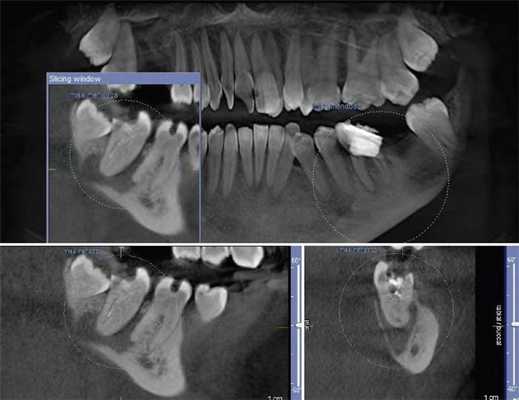

Описаны варианты раздвоения канала нижней челюсти (НЧ), которые были выявлены как случайные находки при конусно-лучевой компьютерной томографии челюстно-лицевой области пациентов, обращавшихся в медицинские центры за стоматологической помощью. Выявленные добавочные каналы в теле НЧ начинались от верхней стенки нижнечелюстного канала и имели небольшую протяженность. Они заканчивались в ретромолярной области, направлялись к корням зубов или ориентировались параллельно основному каналу НЧ.

Удвоение канала нижней челюсти — НЧ (нижнечелюстного канала) — вариант его анатомического строения. О нем имеется упоминание в национальном руководстве по хирургической стоматологии и челюстно-лицевой хирургии [1], а также в ряде научных статей, авторы которых обнаружили дополнительный канал (ы) на анатомических препаратах [2, 3]. Частота выявления нескольких каналов НЧ при анализе ортопантомограмм (ОПМГ) — 0,08—0,95% [4]. Конусно-лучевая компьютерная томография (КЛКТ) выявляет наличие раздвоенного канала в 15,6—64,6% случаев [5—7]. В соответствии с классификацией M. Naitoh и соавт. [5] различают 4 типа канала (рис. 1). Рис. 1. Конфигурация раздвоенного канала НЧ (по M. Naitoh и соавт. [5]). 1-й тип: передний канал — дополнительный канал сливается с основным (а) или оба они идут параллельно (б); 2-й: щечно-язычный канал — расположен со щечной (в) или язычной (г) стороны от основного канала; 3-й: дентальный канал — ведет к корням зубов (д); 4-й: ретромолярный канал — заканчивается ретромолярным отверстием в одноименной ямке (е).

Необычные варианты хода канала НЧ были выявлены как случайные находки при исследовании на КЛКТ челюстно-лицевой области пациентов, которые обращались в медицинские центры Минска в период 2015—2017 гг. за стоматологической помощью. Авторы исследования не ставили перед собой задачу определить частоту встречаемости удвоения канала НЧ в популяции.

Рентгенологическое исследование проводилось на аппарате Galileos GAX5 («Sirona Dental Systems, Bensheim», Germany). Анализ полученных данных проводился по традиционной методике, предусматривающей последовательное изучение сначала срезов в 3 взаимно перпендикулярных проекциях (окно мультипланарной реконструкции), затем срезов, расположенных продольно и поперечно относительно зубной дуги (в окне «Панорама»), а также томограмм произвольной кросс-секции, оптимальной для получения изображений анатомических объектов соответственно их пространственному положению. Оптимальными для визуализации вариантов ветвления канала НЧ являлись реформаты вдоль продольной оси ее тела, которые обозначаются по терминологии разработчиков аппарата как «касательные».

Результаты и обсуждение

Ниже представлены описания рентгенологической картины раздвоенного канала НЧ 3 типов.

Пациентка Е., 48 лет. С левой стороны на уровне угла НЧ от нижнечелюстного канала отходила боковая ветвь (рис. 2). Рис. 2. Ретромолярный канал; КЛКТ пациентки Е., 48 лет. 1 — канал НЧ; 2 — ретромолярный канал; 3 — подбородочное отверстие. Ее поперечный диаметр составлял 1,37 мм у места начала и 0,96 мм в области ретромолярного отверстия.

Поперечный диаметр канала НЧ у места начала ветви — 3,08 мм. Сначала дополнительный канал направлялся вперед. На расстоянии 5,33 мм от места бифуркации он образовывал петлю, менял направления хода и шел назад и вверх, заканчиваясь отверстием в ретромолярной области. Описанный ход характерен для ретромолярного канала (4-й тип раздвоенного канала НЧ). На контралатеральной стороне дополнительных каналов НЧ не обнаружено.

Пациентка Ф., 55 лет. С правой стороны на уровне угла челюсти от верхней стенки нижнечелюстного канала начинался дополнительный канал с поперечным диаметром 1,52 мм (рис. 3, а). Рис. 3. Дентальный канал нижней челюсти. а — КЛКТ пациентки Ф., 55 лет; б — КЛКТ пациентки К., 29 лет. 1 — канал НЧ; 2 — дентальный канал; 3 — подбородочное отверстие. Поперечный диаметр основного канала на этом же уровне — 2,70 мм. Дополнительный канал направлялся полого вперед и вниз параллельно основному каналу НЧ. В мезиальном направлении кортикализация стенок дополнительного канала постепенно уменьшалась, и достоверно проследить его ход удалось до уровня зуба 4.7. Описанная картина характерна для дентального канала (3-й тип раздвоенного канала НЧ). С левой стороны визуализация дополнительного канала была недостоверной: выявлялось линейное просветление такой же локализации и направления, как с правой стороны, но картины трубчатого образования не выявлено, вероятнее всего — вследствие недостаточной кортикализации его стенок.

У пациентки К., 29 лет, с левой стороны обнаружен дентальный канал (см. рис. 3, б). В месте отхождения он имел вертикальный диаметр 1,35 мм (приблизительно в 3 раза меньше вертикального диаметра канала НЧ на этом же уровне), направлялся вперед и вниз, располагаясь параллельно основному нижнечелюстному каналу, и на уровне медиального корня зуба 3.7 круто поднимался вверх. Дентальный канал переставал идентифицироваться на уровне средней трети корня второго нижнего левого моляра. С правой стороны раздвоения канала НЧ не выявлено.

Пациентка Б., 57 лет. С правой стороны на уровне угла НЧ определялась добавочная ветвь нижнечелюстного канала диаметром 1,1 мм, которая, начинаясь от его верхнего контура, далее шла вперед почти параллельно основному каналу на протяжении 8,01 мм, а затем сливалась с ним (рис. 5). Рис. 5. Конфигурация канала НЧ; КЛКТ пациентки Б., 57 лет. 1 — канал НЧ; 2 — передний канал. На контралатеральной стороне добавочных каналов не обнаружено. Описанная рентгенологическая картина соответствует 1-му (а) типу раздвоенного канала НЧ.

По данным литературы, чаще всего встречаются 4-й и 1-й типы раздвоенного канала Н.Ч. Среди прочих вариантов анатомического строения канала они были обнаружены соответственно в 52,5—71,3 и 18,8—44,3% случаев [4—7]. Щечно-язычный и дентальный тип канала выявлялись в 0,5—8,3% наблюдений. В общей популяции, по данным L. Haas и соавт. [8], на ОПМГ и КЛКТ-сканах частота встречаемости ретромолярного канала составляет 4,20%, а всех других типов раздвоенного канала — 16,25%.

Канал НЧ при типичной локализации визуализируется в виде трубчатого костного образования, стенки которого представлены тонкими линейными затемнениями кортикальных пластинок, а содержимое канала отображается в виде интенсивного просветления. Калибр канала постепенно уменьшается в мезиальном направлении. Достоверным признаком наличия дополнительного канала является продолжение в его стенку кортикальной пластинки основного канала. Это дает возможность проследить дополнительный канал на всем его протяжении. У места его начала канал НЧ, как правило, имеет локальное расширение. Дополнительные каналы обычно отходят от верхней стенки канала НЧ и имеют небольшую протяженность.